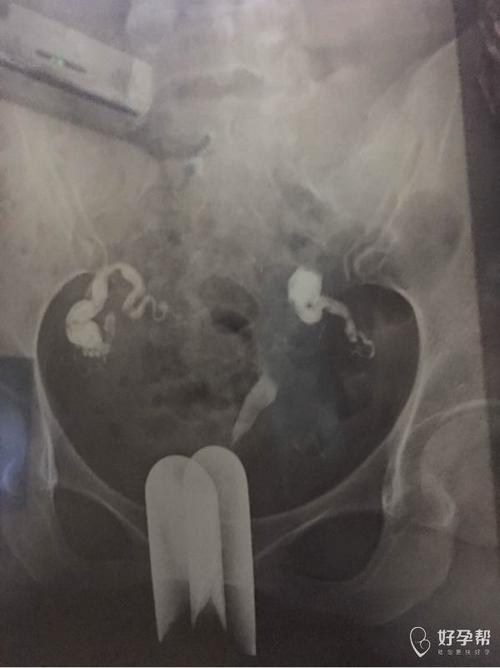

输卵管积水

输卵管积水是指输卵管内口或者内口的积水,它的范围还是存在的,但是输卵管还是有问题的。另外,当输卵管内的积水和卵泡液的形成是,输卵管的纤毛受到过度的拉制,例如爆弹、钳夹,只要没有伤害到输卵管。如果输卵管管腔还是完整的,那就是可以怀孕的,如果积水比较多,那么积水就会出现在沟渠以及阴道处,这也是排卵性的。